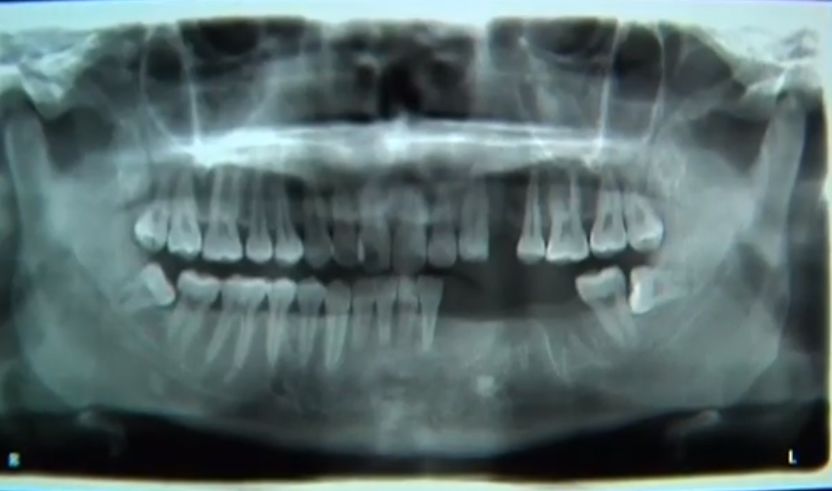

当时轮胎弹起来后,轮毂直接打到了小王脸颊,这一下不仅将小王撞到了两米开外,还在他的左边脸颊上留下了恐怖伤口,幸好当时家里人就在旁边,马上拨打120急救电话将他送到医院进行救治。经过检查,除了脸颊上的伤口外,小王还被打断了五颗牙齿。之后经过一个多月的休养,伤口总算慢慢愈合了。但家人明显感觉到小王说话比以前少了。

这位负责人告诉记者,事情发生后市场监督管理局也有介入,厂家答应给5000元,他们也多次前往进行协调,但小王一方始终不同意。对此小王母亲钱女士表示,儿子光前期医药费就花了五六千,后面光种植牙齿还要大几万,这点补偿根本不够。